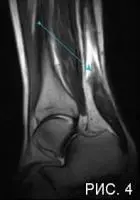

На МР-томограмме показан разрыв ахиллова сухожилия: сухожилие в нижних отделах утолщено, выше стрелки, белым визуализируется место разрыва, в виде локального отека. (Рис 4).